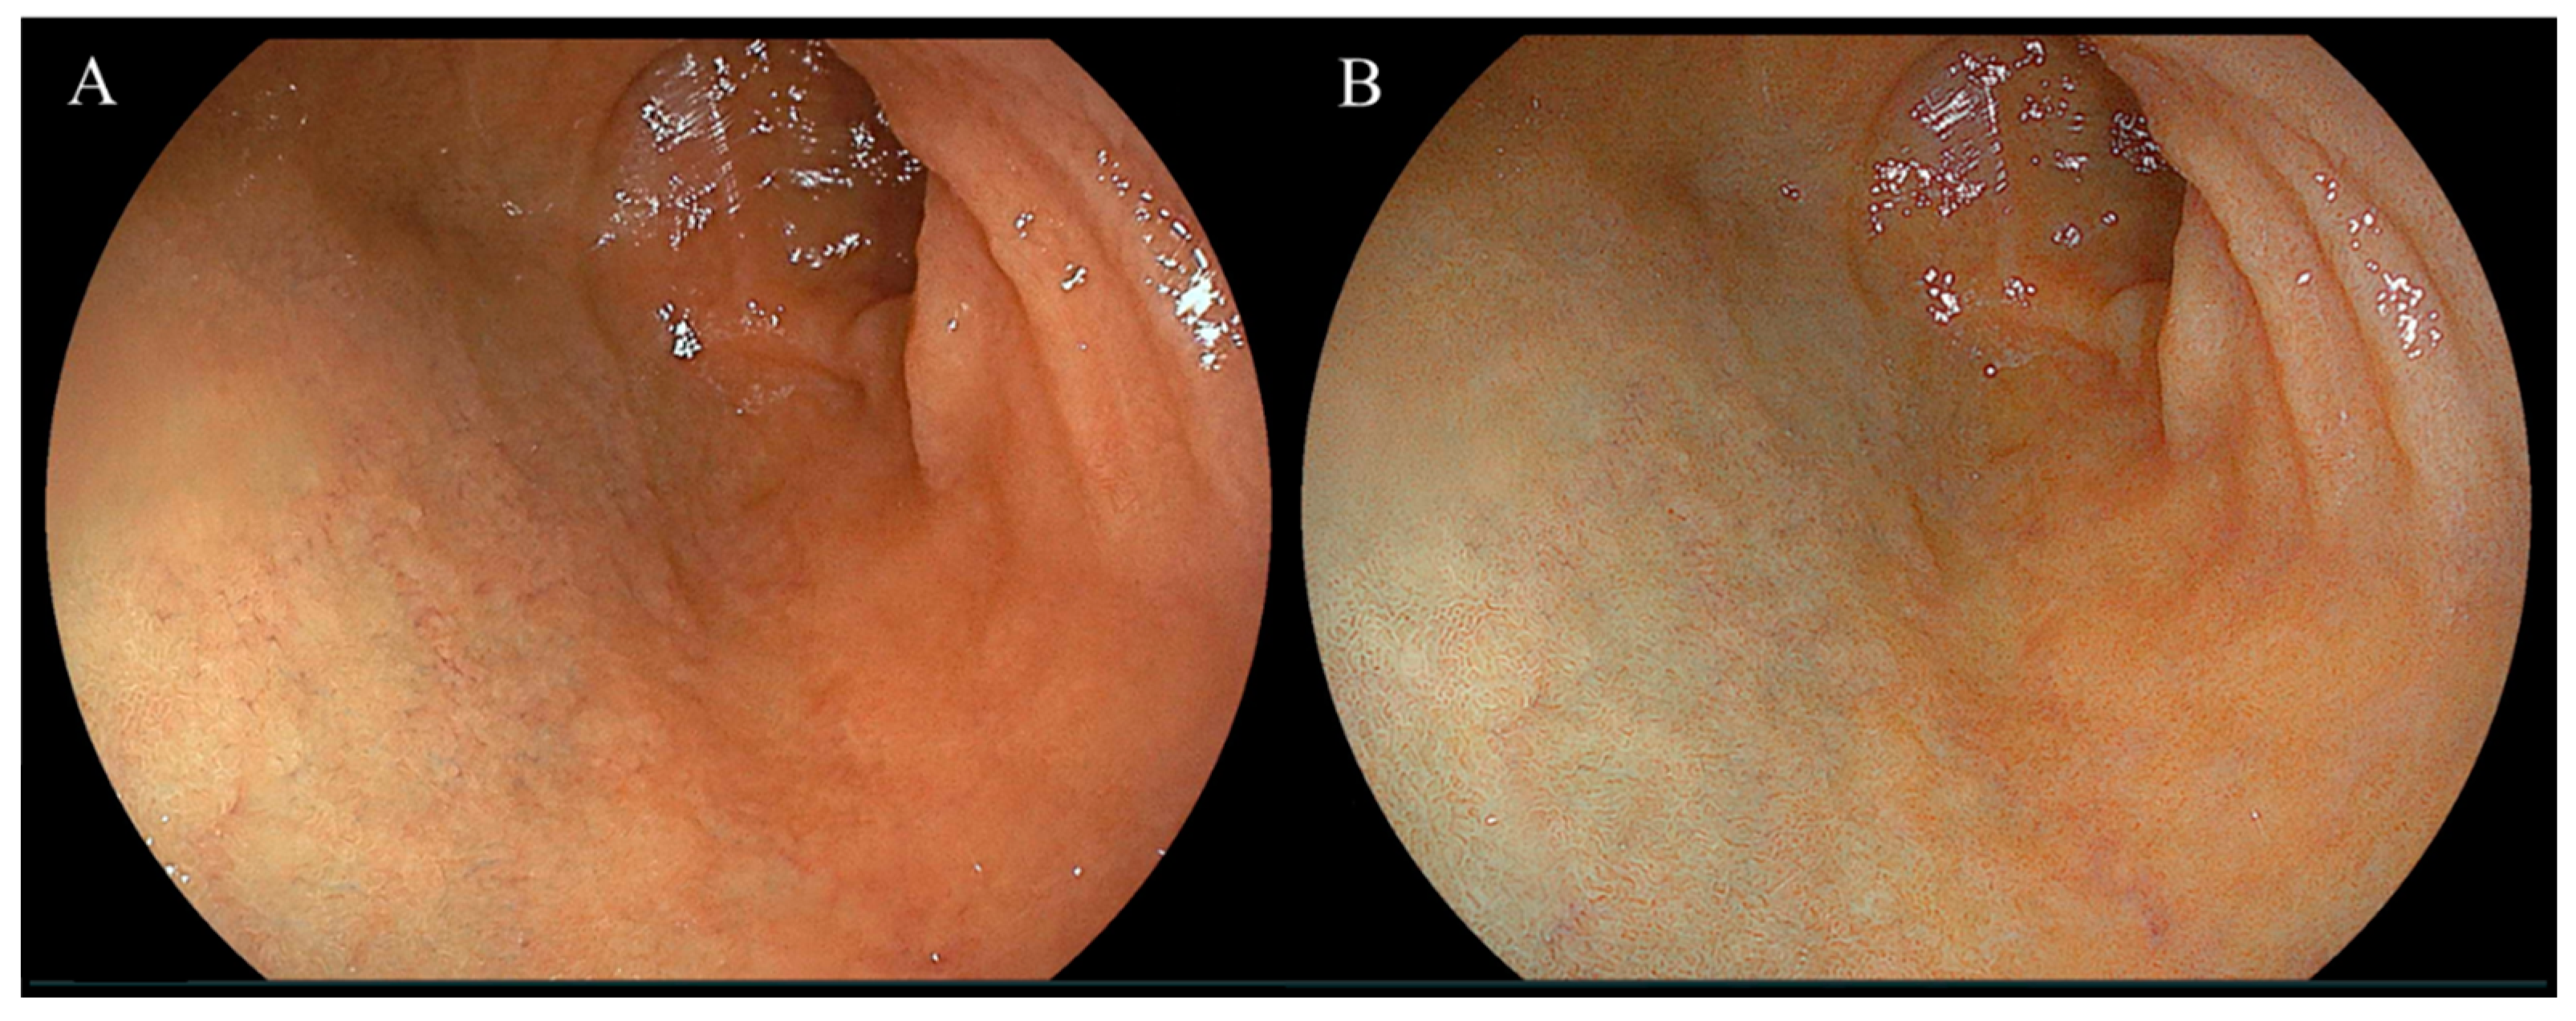

Endoscopic images taken in the duodenal mucosa of bulbs, with or without red mucosa, are shown in Figure 2 and Figure 3, respectively. Approximately 21 out of 302 (7.0%) cases were in the redness (+) group and the concordance rate between the two assessors was 86.4% (261/302). Figure 4 presents endoscopic images after the use of WLI and LCI with ROIs. An analysis of L* a* b* color values for the duodenal bulb was carried out (Table 3). White light imaging and LCI showed significant differences between the L* a* b* color values. The red component (a*) of the duodenal bulb with LCI was significantly higher than that using WLI in the redness (+) group but was found to be significantly lower in the redness (−) group. Comparing the L* a* b* color values between redness (+) and (−) groups, the a* values were significantly higher in the redness (+) group for both WLI and LCI (p < 0.001). However, a difference was not observed in b* values with LCI (WLI: p = 0.021, LCI: p = 0.338). Subjective evaluation showed that the redness (+) group consisted of 7% of 302 cases. Objective evaluation showed that the red component (a*) of the duodenal bulb with LCI was significantly higher than WLI in the redness (+) group.

Figure 2.

Representative endoscopic images of the duodenal mucosa of bulbs showing red mucosa using white light imaging and linked color imaging. (A) White light imaging (WLI). Duodenal mucosa of bulbs. (B) Linked color imaging (LCI). The duodenal mucosa of bulbs was accentuated in a red color using LCI.